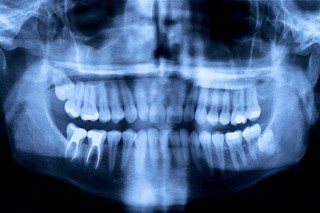

Nedan finns en lista med behandlingar som vi utför. Klicka på knapparna för att läsa mer om just den behandlingstypen🦷